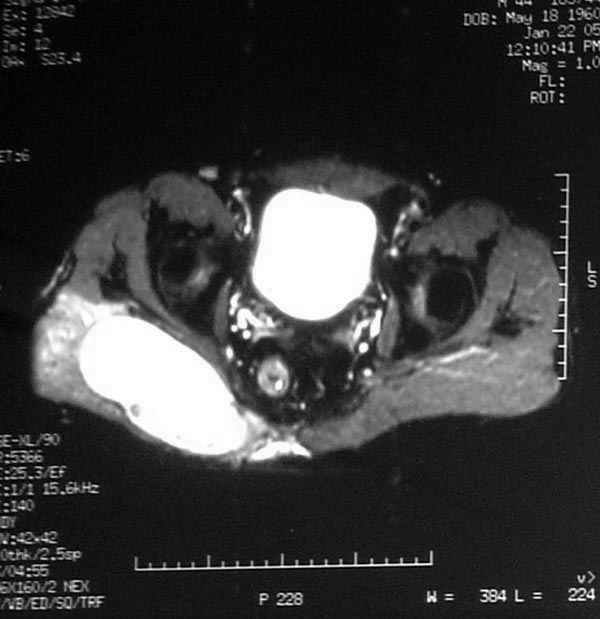

Уважаемые коллеги,Неоднократные пункционные эвакуация (3 раза) крови изягодичной области, после полученной пройзводственнойтравмы (более 1.5 мес) ударом в ягодицу тяжелым, около полутонны предметом.

Рентгенограмма без особенностей, несмещенные переломы лонной и седалищных костей таза.Последная пункция 10 дней назад 180 мл темной крови, после пункции сделано магнито-резонансные исследование (на снимках), какой диагноз и тактика дальнейшего лечения, какие рекомендации?Джолдас Кульджанов

Разбираемый случай немного отличался от классического Degloving Injury

или Morel-Lavalle Lesion, которые часты при переломах ацетабулума и

костей таза. Состояние, наблюдаемое после удара, в результате чего

образуются обширные полости в тазобедренной области: ягодицы или

большого вертела. Как описал Анатолий, обширные полости заполняются

кровью, затем синовиальной жидкостью, отодвигают сроки операции или

после операции приводят к осложнениям послеоперационных ран.

Описанный случай:

В промежутке около месяца 3 пункции с удалением около 180 мл крови

каждый раз. После исследовании МРТ было принято решение - удаление

гематомы в операционной более широким доступом. Во время операции -

под ягодичной мышцей была капсула, где скопилось около 700 мл

гематомы, после удаления в полости обнаружили несколько закупорившихся

вен и краевой разрыв одной из двух ветвей нижней ягодичной артерии.

После промывания, гемостаза и дренажа, по рекомендации хирурга стенку

полости обработали спреем Tisseel, специальным склерозирующим

препаратом, применяемым пластическими хирургами, затем зашили рану.

Дренажи удалены на 5 день, рана зажила первично. Случай был интересен

применением препарата Tisseel Fibrin Sealant для склерозирования

полостей, только недавно получившим разрешение к применению, хотя по

аннотации в Европе и в Южной Америке применяют давно.